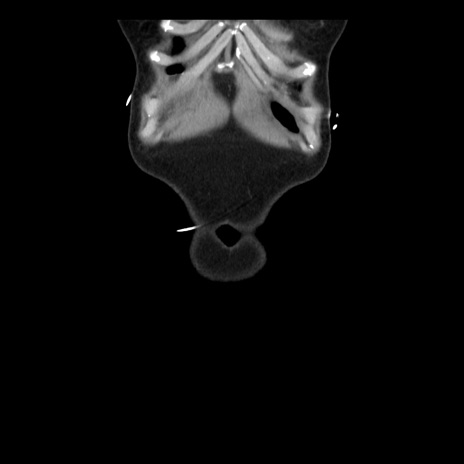

矢状断像